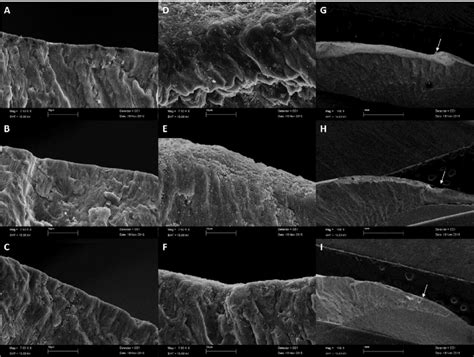

• Representative Scanning Electron Micrographs Of The Enamel Cross ...